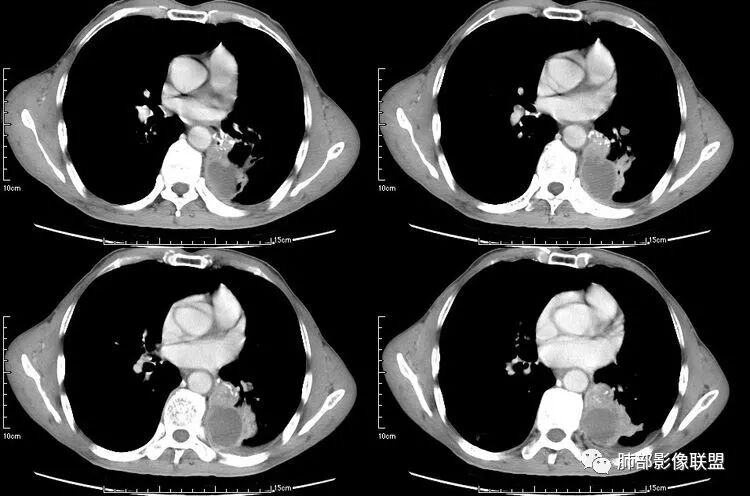

患者老年男性,咳嗽、咳痰、痰中带血伴胸闷2月余。长期大量吸烟史。查肝肾功能、血糖、血脂、心肌酶、电解质、血沉、C反应蛋白、抗“O”、类风湿因子、抗核抗体谱无明显异常。肿瘤标志物提示NSE、CYFRA21-1稍升高。胸部CT:肺气肿背景,左肺下叶后基底段不规则肿块影,见支气管截断,内见大片状低密度区及部分血管影,增强轻度强化,远端空洞形成。双肺多发不规则实性结节影、见毛刺、胸膜牵拉及血管集束,结节内见空洞形成,部分可见血管影,多位于胸膜下。双肺见多发肺大泡。综合考虑左下肺恶性病变并双肺转移。鳞癌或淋巴瘤可能。鉴别血管炎性病变及真菌感染。

左肺下叶团块病灶,有明显张力,增强后病灶内部有可疑延迟强化,看不清楚病灶与支气管的关系,应该支气管受压阻塞了,双肺多发胸膜下小结节,病灶小结节病灶有平行胸膜生长的表现,部分小结节厚壁,部分薄壁,,还有一部分有内容物,这需要两元论,左肺下叶肺癌(腺癌)伴转移,同时合并真菌感染。

液化,而不像坏死,是有强化的;这个里面似有液平。说明里面有分泌粘液?

无发热,其他慢性细菌先不考虑,有的低毒的,但是结节形态还是比较不规则的,分布也是比较随机,更像原发病灶。真菌方面,结节没有融合,坏死也是液化坏死,不符合隐球菌,曲霉不符合IPA,慢性吸入的也少见。结核没有树丫,不考虑。鉴别主要是GPA,和肺癌。GPA不支持点是皮肤,肾脏没有累及,ANCA不支持。。。肺癌主要是腺癌和鳞癌转移。比较支持的是淋巴结肿大,和左下肺的主病灶,支气管堵塞和异常强化。还有分叶,局部膨隆。可以建议支气管镜检测。

本病例左肺下叶肿块,有深分叶、毛刺、胸膜牵拉凹陷、支气管截断及纵隔内淋巴结肿大等征象,都均支持病灶为恶性,如腺癌,而且叶间裂的多发结节也提示是腺癌来源可能大;双肺多发结节、肿块,大部分病灶有分叶、毛刺及胸膜凹陷的恶性征象,与原发肿瘤本身的性质有关,所以应该与左肺下叶肿块同源,而且双肺多发病灶内空洞也具有多样性;